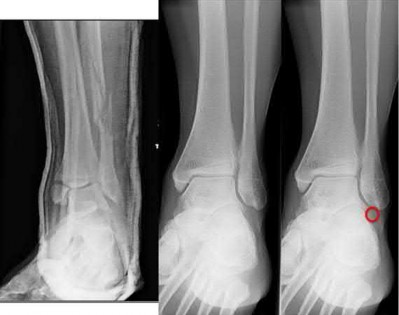

A 25-year-old male sustains an ankle fracture dislocation and undergoes open reduction and internal fixation. He returns to clinic five months following surgery complaining of continued ankle pain and instability with weight bearing. His immediate post-operative AP radiograph is seen in Figure A. Which of the following could have prevented this patient from developing persistent pain?

The patient presents with continued ankle pain and instability following open reduction and internal fixation. The radiograph in figure A demonstrates inadequate restoration of fibular length, likely leading to continued tibiotalar instability.